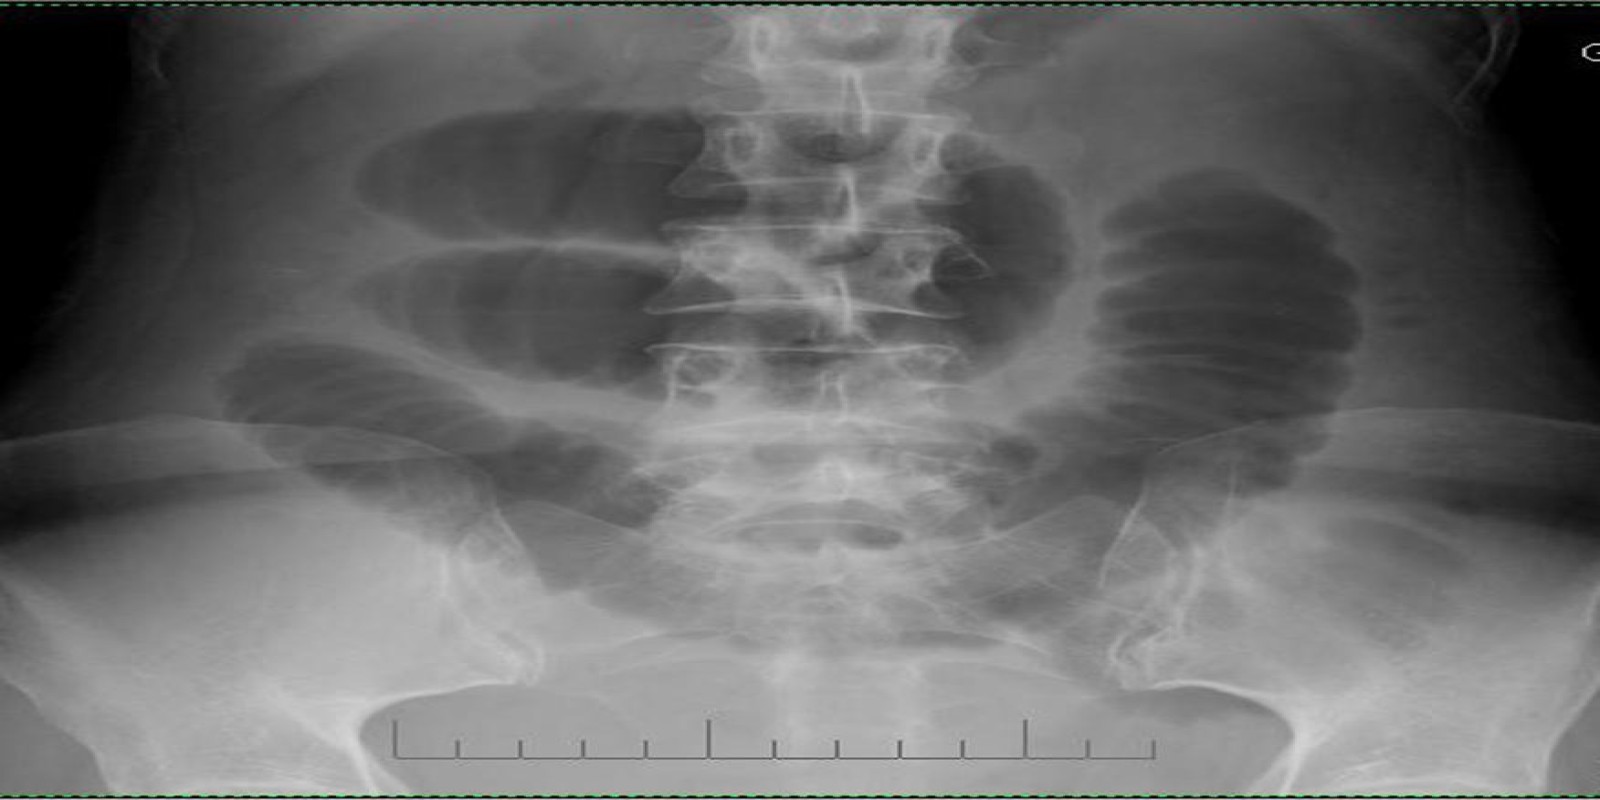

Caso Código 002D de Obstrução Intestinal do Delgado

Cod.: 002D